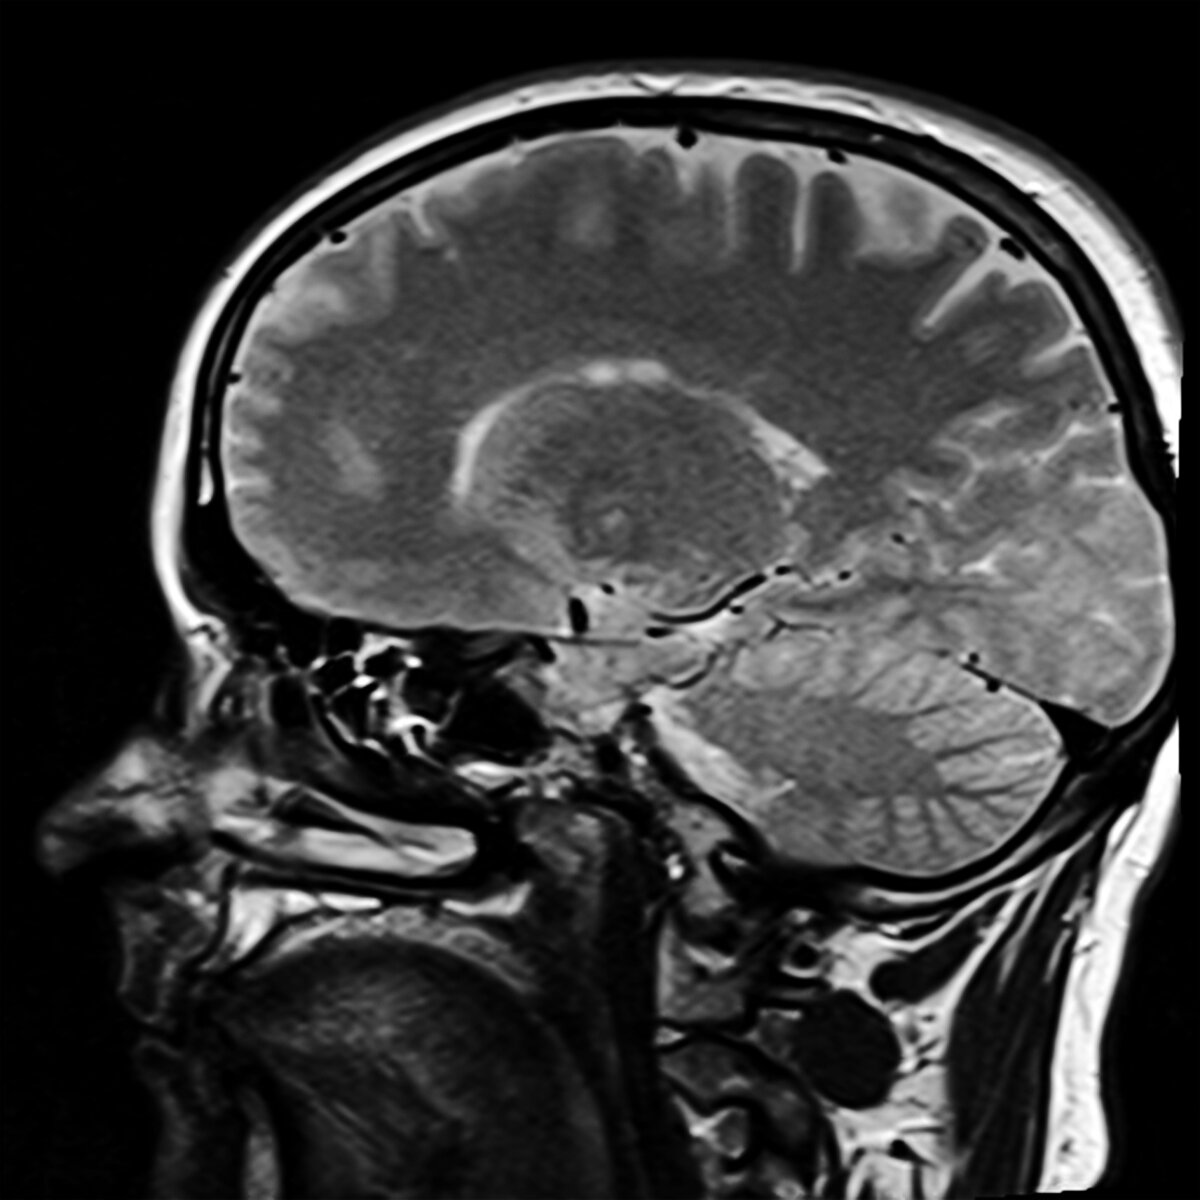

МРТ или магнитно-резонансная томография — это объективный метод исследования состояния внутренних органов. Результатом являются объемные или обычные снимки. Их описанием и расшифровкой занимаются специально обученные врачи-диагносты. Они владеют обширным уровнем медицинских знаний, а также умеют грамотно читать рентгеновские снимки. В статье подробнее разберем — что входит в обязанности специалиста, где работает и сколько получает врач МРТ, какой уровень образования необходим для работы.

Метод МРТ выявляет патологические процессы, которые происходят в мягких тканях. От качества проведенного исследования зависит точность диагноза и правильность назначенного лечения. При помощи томографии исследуются практически все части тела человека — от головы, позвоночника до суставов.